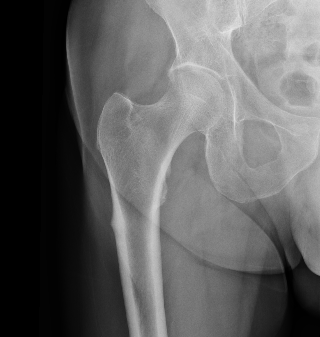

Atypical FFAFF incomplete

Incomplete subtrochanteric AFF

Stress Fracture Lateral

Incomplete femoral shaft AFF / dreaded black line

Femoral stress fracturecomplete AFF

Complete AFF